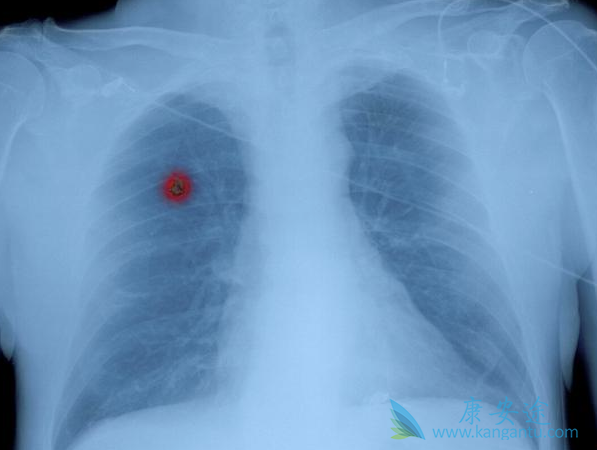

在医生眼里,肺癌分4期,1(I)、2(II)、3(III)、4(IV)期,每一期又分a和b,比如1a和1b期,1a期是最早期的肺癌,1b也属早期,但比1a期相对来说稍晚。在我们老百姓眼里,癌症怎么都得分个早中晚期,虽然这种分法不甚科学,但是长此以往医生也顺应了这种说法,一般来说,1期肺癌属于早期。2a期属于中期偏早,2b和部分可手术的3a期属于中期,另外一部分无法手术根治的3a期则属于中期偏晚。3b期和4期肺癌归结为晚期肺癌。什么样的肺癌才属晚期?肺癌,顾名思义长在肺上,那么如果肺脏以外的器官出现了转移(metastasis,M),可以直接定义为晚期,比如骨转移,脑转移,肾上腺转移,肝转移等,如果出现了多器官多部位的转移,那么就是晚期中的晚期了。

其实吧,晚期肺癌最容易出现转移的部位是肺脏本身,如果肺脏本身出现了多发的转移结节,尤其是右侧肺癌出现了左肺转移或者左肺癌出现了右肺转移,这也是晚期肺癌。再来说淋巴结转移,肺癌出现了淋巴转移可不一定属于晚期,或者可以这么说,不管淋巴结转移的有多么厉害,都不属于4期,最多是3B期肺癌。淋巴结转移根据部位的不同,2a、2b、3a、3b期肺癌都可能会伴有淋巴结的转移,只不过淋巴结转移的部位不同而已,离原发病灶越远的淋巴出现转移,则提示分期越晚。3b期和4期肺癌因为往往无法获得根治,注意这里我的用词是往往,仍然有很少部分的晚期肺癌经过积极治疗是可以根治的。而我这里要提的是那些无法获得根治的晚期肺癌,那么我们的治疗目标就是尽可能延长患者的生命,并保证一定的生活质量。晚期肺癌治疗后可以存活10年以上,早就不是梦了。